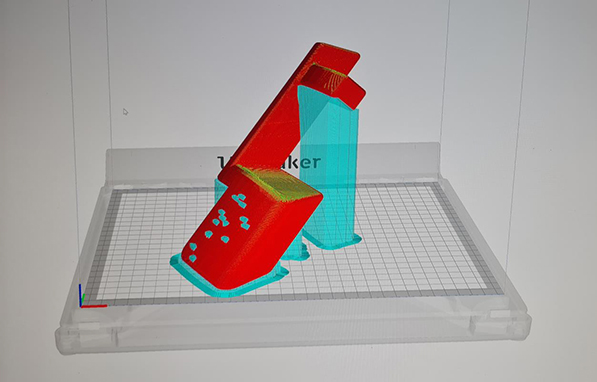

Dizajn vodiča obrađen

za 3D štampanje |

Trodimenzionalno štampanje je generalno nova tehnologija koja omogućava da se prema digitalnom modelu nekog predmeta, nanošenjem tankih slojeva odabranog materijala, izradi realan trodimenzionalni predmet. Prema ovoj definiciji, 3D štampanje omogućava izradu i repliciranje bilo kog predmeta, pa tako i izradu personalizovanih hirurških instrumenata - PSI (Personalized Surgical Instruments), što je jedna od primena ove vrste tehnologije u ortopedskoj hirurgiji. Najćešće se izrađuju takozvani vodiči za uvođenje hirurških alatki u telo pacijenta, ili vodiči za sečenje kod nekih procedura (npr. kod ugradnje veštačkog kolena), koji se dizajniraju prema individualnim morfološkim karakteristikama kosti/zgloba acijenta.